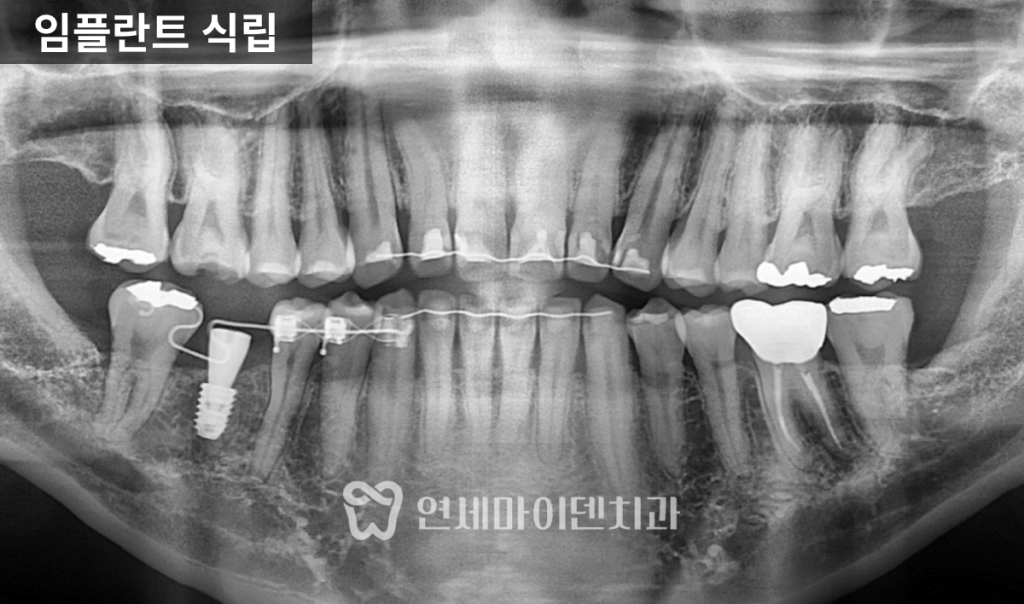

목표로 해야 합니다.임플란트 식립과 마무리

공간 확보 후

임플란트를 정확한 위치에 식립했습니다.임플란트가 뼈와 안정적으로 결합되는 동안

교정을 병행해 공간을 유지했고,최종적으로 교합 간섭 없이

자연스러운 씹는 기능을 회복했습니다.

교정 전과 비교하면

임플란트 공간은 체감상 두 배 이상 확보되었고

다른 치아들의 불필요한 이동 없이

치료가 안정적으로 종료되었습니다.협진이 중요한 이유